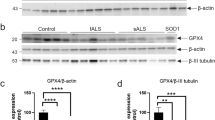

Quantitative analysis of the vacuoles, LBHIs and motor neurons in the lumbar segment of G1L and G1H mice

Figure 5 shows the number of small (<5 μm) and large (>5 μm) vacuoles, and LBHIs and motor neurons (>25 μm) in the lumbar segment during the clinical course of the disease in G1L mice. Numerous small vacuoles were already evident at 90 days, and their number decreased as the disease progressed (Fig. 5a, Table 1, P<0.05). The number of large vacuoles, which appeared at around 140 days, were increased significantly by 180 days but then decreased significantly by 230 days (Fig. 5a, Table 1, P<0.05). The ratio of the number of large vacuoles to the total number of vacuoles was 10–20% at 140 and 180 days, and ~50% in moribund mice (Fig. 5a). In G1H mice, the total number of vacuoles showed a tendency to decrease, but not to a significant degree (Table 1, P=0.1266). The number of neurons declined significantly after 180 days in G1L mice, and after 66 days in G1H mice (Table 1, P<0.05). LBHIs were restricted to the anterior horn at 180 and 100 days in G1L and G1H mice, respectively, becoming more widespread at the later stages. The number of LBHIs increased significantly in G1L or G1H mice as the disease progressed (Fig. 5b, Table 1, P<0.05). Most of the LBHIs were intra-neuritic.

Correlation between the numbers of vacuoles and LBHIs in symptomatic G1L and G1H mice

Figure 6 shows the correlation between the numbers of vacuoles and LBHIs observed in symptomatic G1L (230 days and in the moribund state) and G1H (100 and 115 days) mice. The number of vacuoles in G1H mice was greater than in G1L mice. Regression analysis revealed a statistically significant inverse correlation between the numbers of vacuoles and LBHIs in both G1L (r=−0.91, P<0.01) and G1H (r=−0.93, P<0.01) mice.

Inverse correlation between the numbers of mitochondria-derived vacuoles and LBHIs. A statistically significant inverse correlation was observed between the numbers of LBHIs and vacuoles in both G1L (green) and G1H (orange) mice. Numbers shown in italics represent the age of the G93A mice at perfusion